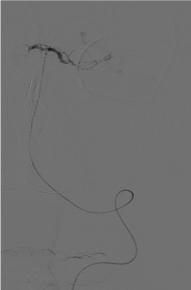

Peripheral venous heparinization, heparin dosage is 60 U/Kg, and 6F guided catheter tip is placed into the responsible artery (vertebral artery or carotid artery) under the guidance of hyper slip guide wire. On the road map, rebar-18 or rebar-27 (EV3 Inc, USA) microcatheter tip reaches the distal end of the thrombus, and the microcatheter is clearly defined in the vascular cavity, as shown in Figure 3.

Figure 3. Microcatheter tip reaches the distal end of the thrombus, and the microcatheter is clearly defined in the vascular cavity